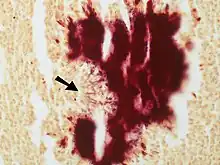

Colony of Actinomyces surrounded by macrophages.. A Gram stain is needed to see the filamentous organisms. Large colonies of Actinomyces can appear macroscopically as yellow granules whch have been termed "sulfur granules".